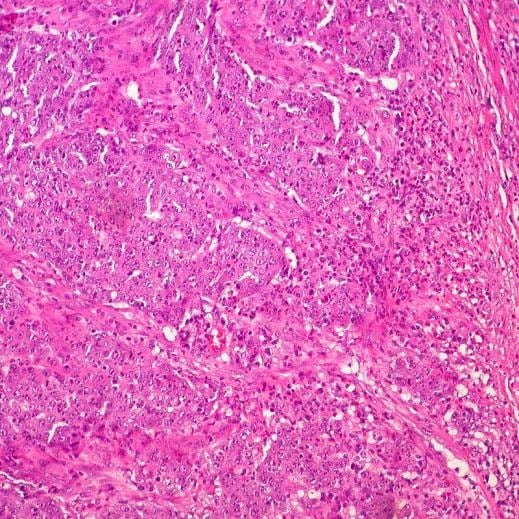

El cáncer colorrectal, también denominado cáncer de colon, surge por el crecimiento anómalo de células en el colon o el recto. En muchos casos se inicia en pólipos benignos que pueden tardar entre diez y quince años en transformarse en tumores malignos, según datos de la Fundación GEDYT. Ese largo proceso ofrece una ventana de oportunidad para detectar y extirpar lesiones antes de que evolucionen.